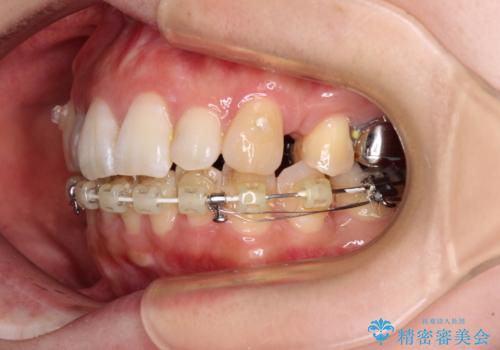

- ハーフリンガル

目立たない装置が希望であったため、上顎が裏側装置である、ハーフリンガル装置を選択されました。